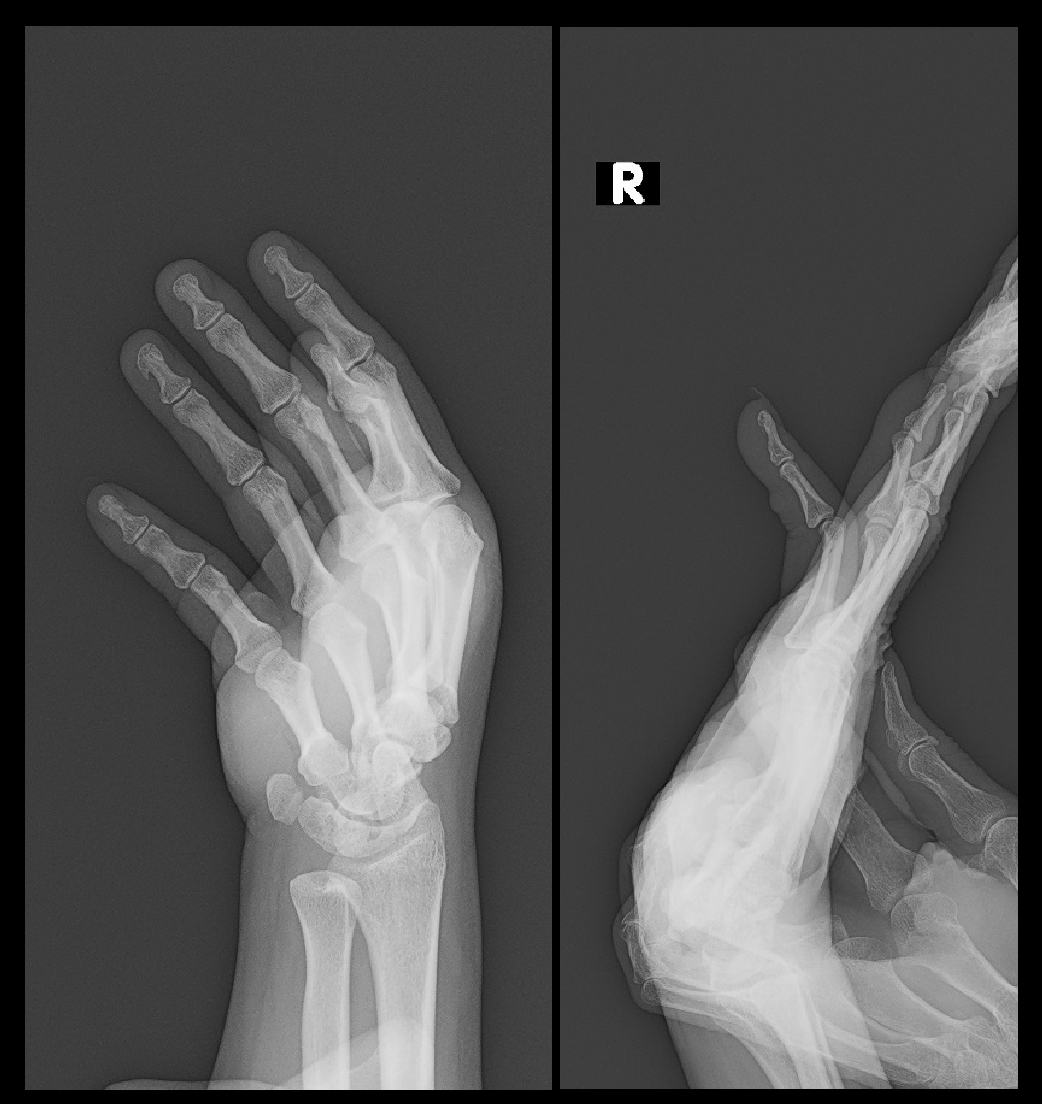

手指の外傷によるボタン穴変形という変形障害があります。ちょっとしたケガで発症することも多いのですが、その治療はけっこう困難でうまく行かない場合もあり、生涯にわたり変形が残ることも少なくありません。私は卒後10年ぐらいまでは千葉大学で手の外科を専門とする整形外科医でしたが、大学の手の外科診療でうまくボタン穴変形を治療できたという記憶が残っていません。開業後の診療でうまく治療できなかった症例を提示しますが、まず手指の関節の呼び方を提示します。整形外科医は和名が長いため、英語の略称で手指の関節を表現しています。

手指の関節.jpg

41才女 Xp1.jpg

レントゲン像は、脱臼は整復されていて問題ありません。初診時、右小指は環指(薬指)とともに伸展位固定をしています。またボタン穴変形について、治りが悪い変形であることも説明しています。